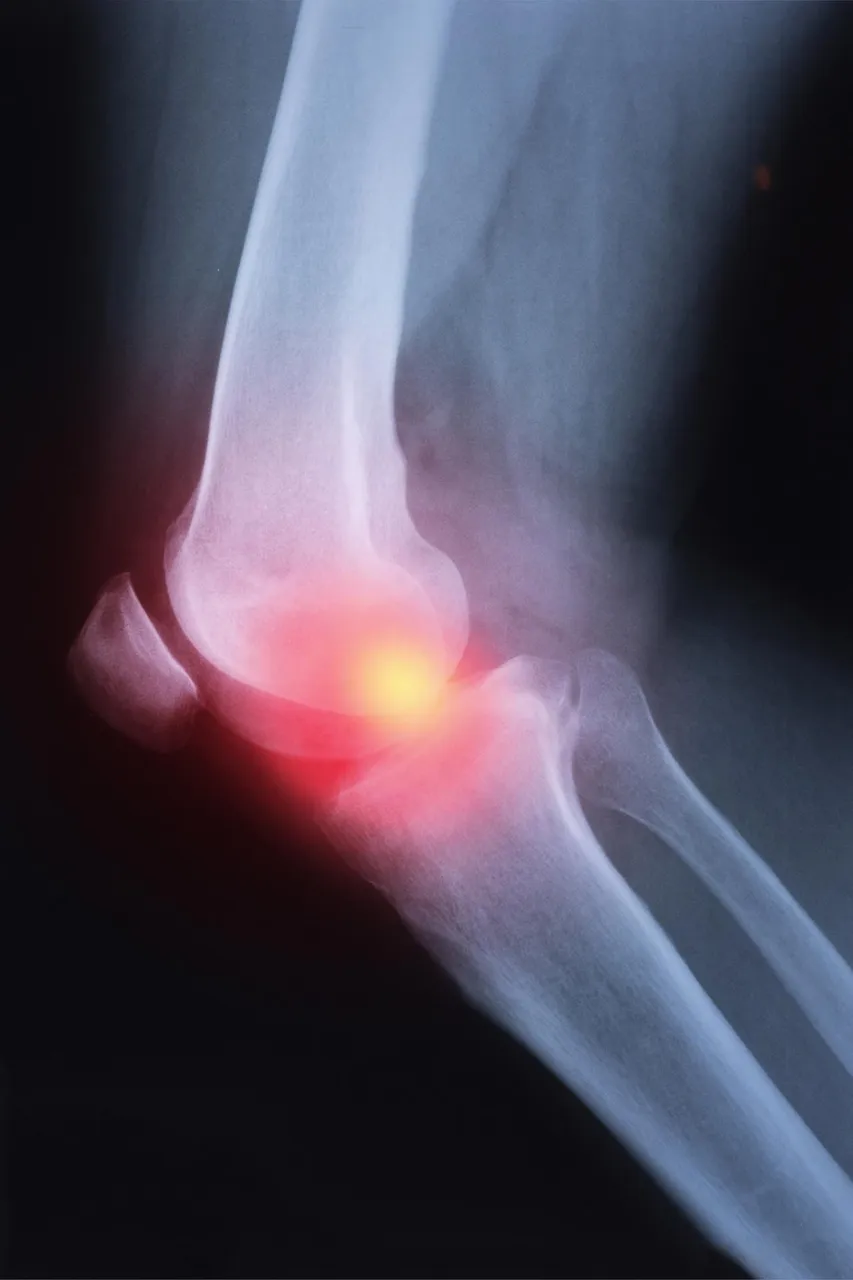

研究人员首次表明,一类抗纤维化药物能抑制类风湿性关节炎(RA)患者的间质性肺病(ILD)的进展。根据美国国立犹太卫生院的部分研究,吡非尼酮被证明对这些人是安全和有效的。这项研究于本月早些时候发表在《柳叶刀呼吸医学》杂志上,是第一个针对RA-ILD患者的前瞻性治疗试验。据估计,有130万美国人患有类风湿性关节炎。

国家犹太卫生中心间质性肺病项目主任、该研究的第一作者约书亚-所罗门博士说:"ILD是RA患者中相对常见的并发症,在这些患者中,有高达10%的患者可能会发展并导致过早死亡。这项研究带来的发现对患有RA-ILD的病人来说是一个很大的进步"。

类风湿性关节炎(RA)是世界上最常见的自身免疫性疾病之一。类风湿性关节炎和间质性肺病治疗1(TRIAL1)是一项随机、双盲、安慰剂对照的2期试验,在四个国家的34个专门研究ILD的学术中心完成。RA-ILD患者接受了52周的吡非尼酮(一种抗疤痕的药物)或安慰剂治疗。